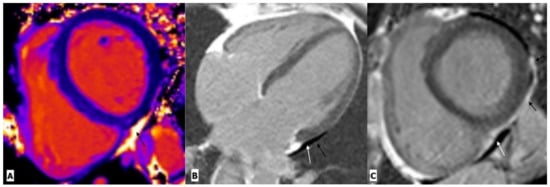

2.1. Myocarditis

| Myocarditis | Luetkens, J.A. et al. | Prospective cohort study | 28 patients and 22 control subjects | CMR | Compared with healthy controls, HIV-infected patients showed lower ejection fraction, lower global strain values, elevated native T1 and T2 values, and myocardial fibrosis, predominantly at the subepicardial of the midventricular and basal inferolateral wall. |

| Ntusi, N. et al. | Cross sectional observational study | 103 patients and 92 control subjects | CMR | Compared with controls, HIV-infected patients had lower LVEF, higher myocardial mass, lower peak diastolic strain rate, and higher native T1 values. Pericardial effusions and myocardial fibrosis were 3 and 4 times more common, respectively, in subjects with HIV infection. | |

| Robbertse et al. | Prospective study | 73 patients and 22 healthy controls | CMR | Compared with controls, a significant decrease in native T1 and ECV was seen after 9 months of HAART in HIV patients, which was significantly associated with a decrease in C-reactive protein, a decrease in HIV viral load, and an improvement in CH4 count. | |

| De Leuw et al. | Prospective observational study | 156 patients | CMR | Patients with higher ECV values have a higher rate of cardiovascular outcomes. | |

| de Leuw, P. et al. | Prospective observational longitudinal study | 156 HIV infected patients | CMR | Patients with higher native T1, native T2, and LV mass indexes have higher events. In multivariable analyses, native T1 was independently predictive of adverse events. Traditional cardiovascular risk scores were not predictive of adverse events. | |